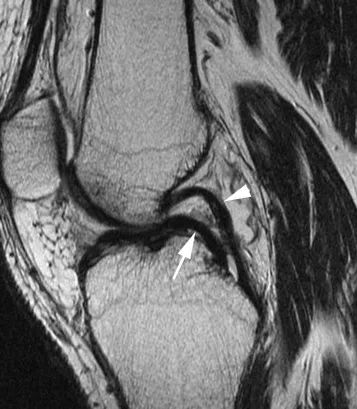

Наиболее частой находкой является прямая визуализация мигрирующих отломков в межмыщелковой области: ориентир «двойной задней крестообразной связки (ЗКС)» характерен при повреждении медиального мениска и интактности передней крестообразной связки.Вывихнутый сегмент выглядит как дугообразная гипоинтенсивная полоса, параллельная нормальной задней крестообразной связке, создавая вид «двойной ЗКС» (рис. 7).Избыточные грабельные рожки (размером более 6 мм) также могут свидетельствовать о наличии рукоятки ствола (рис. 8).В этом случае вывихнутый фрагмент мениска прикрепляется к здоровому переднему рогу.

Рисунок 7 Внешний вид рукоятки медиального мениска имеет признак «двойной ЗКС».Сагиттальный PD-взвешенный вид с подавлением жировой ткани: смещенный фрагмент мениска (стрелка) лежит ниже нормальной ЗКС (стрелка) и образует характерный вид «двойной ЗКС».